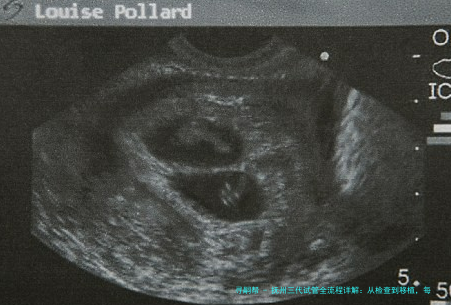

B超检查:当血HCG水平上升到一确定数量值后,医生会安排B超检查,认定是否是成功着床并观测胎心。